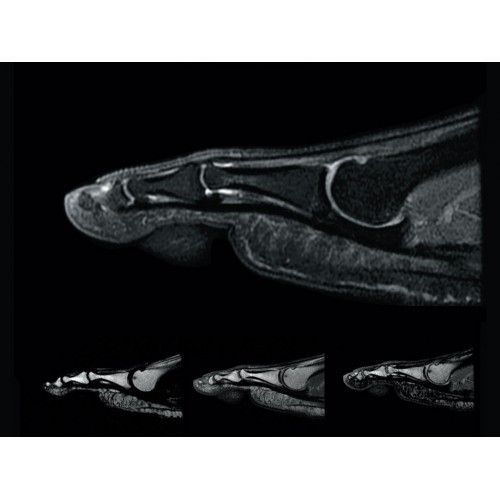

• РЧ-катушки, оптимизированные для исследования конкретных участков тела — элементы катушек высокой плотности располагаются вокруг исследуемых участков тела и при необходимости обеспечивают расширенный охват и оптимальное качество изображений при каждой процедуре.

• Широкое поле зрения — поле зрения шириной 50 см позволяет охватывать крупные анатомические области за меньшее число сканов.